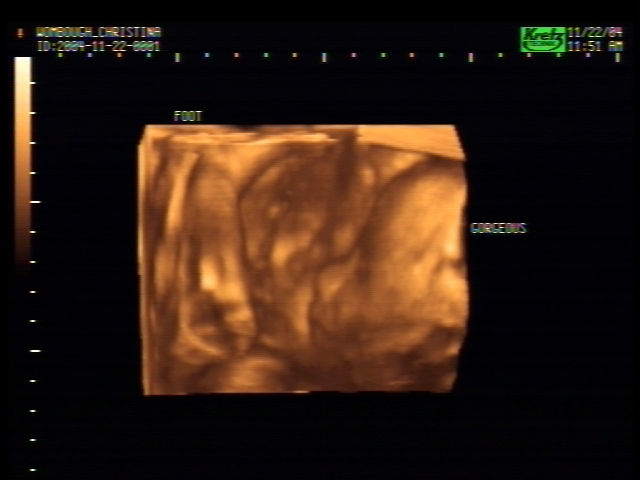

3D Sonogram Pictures